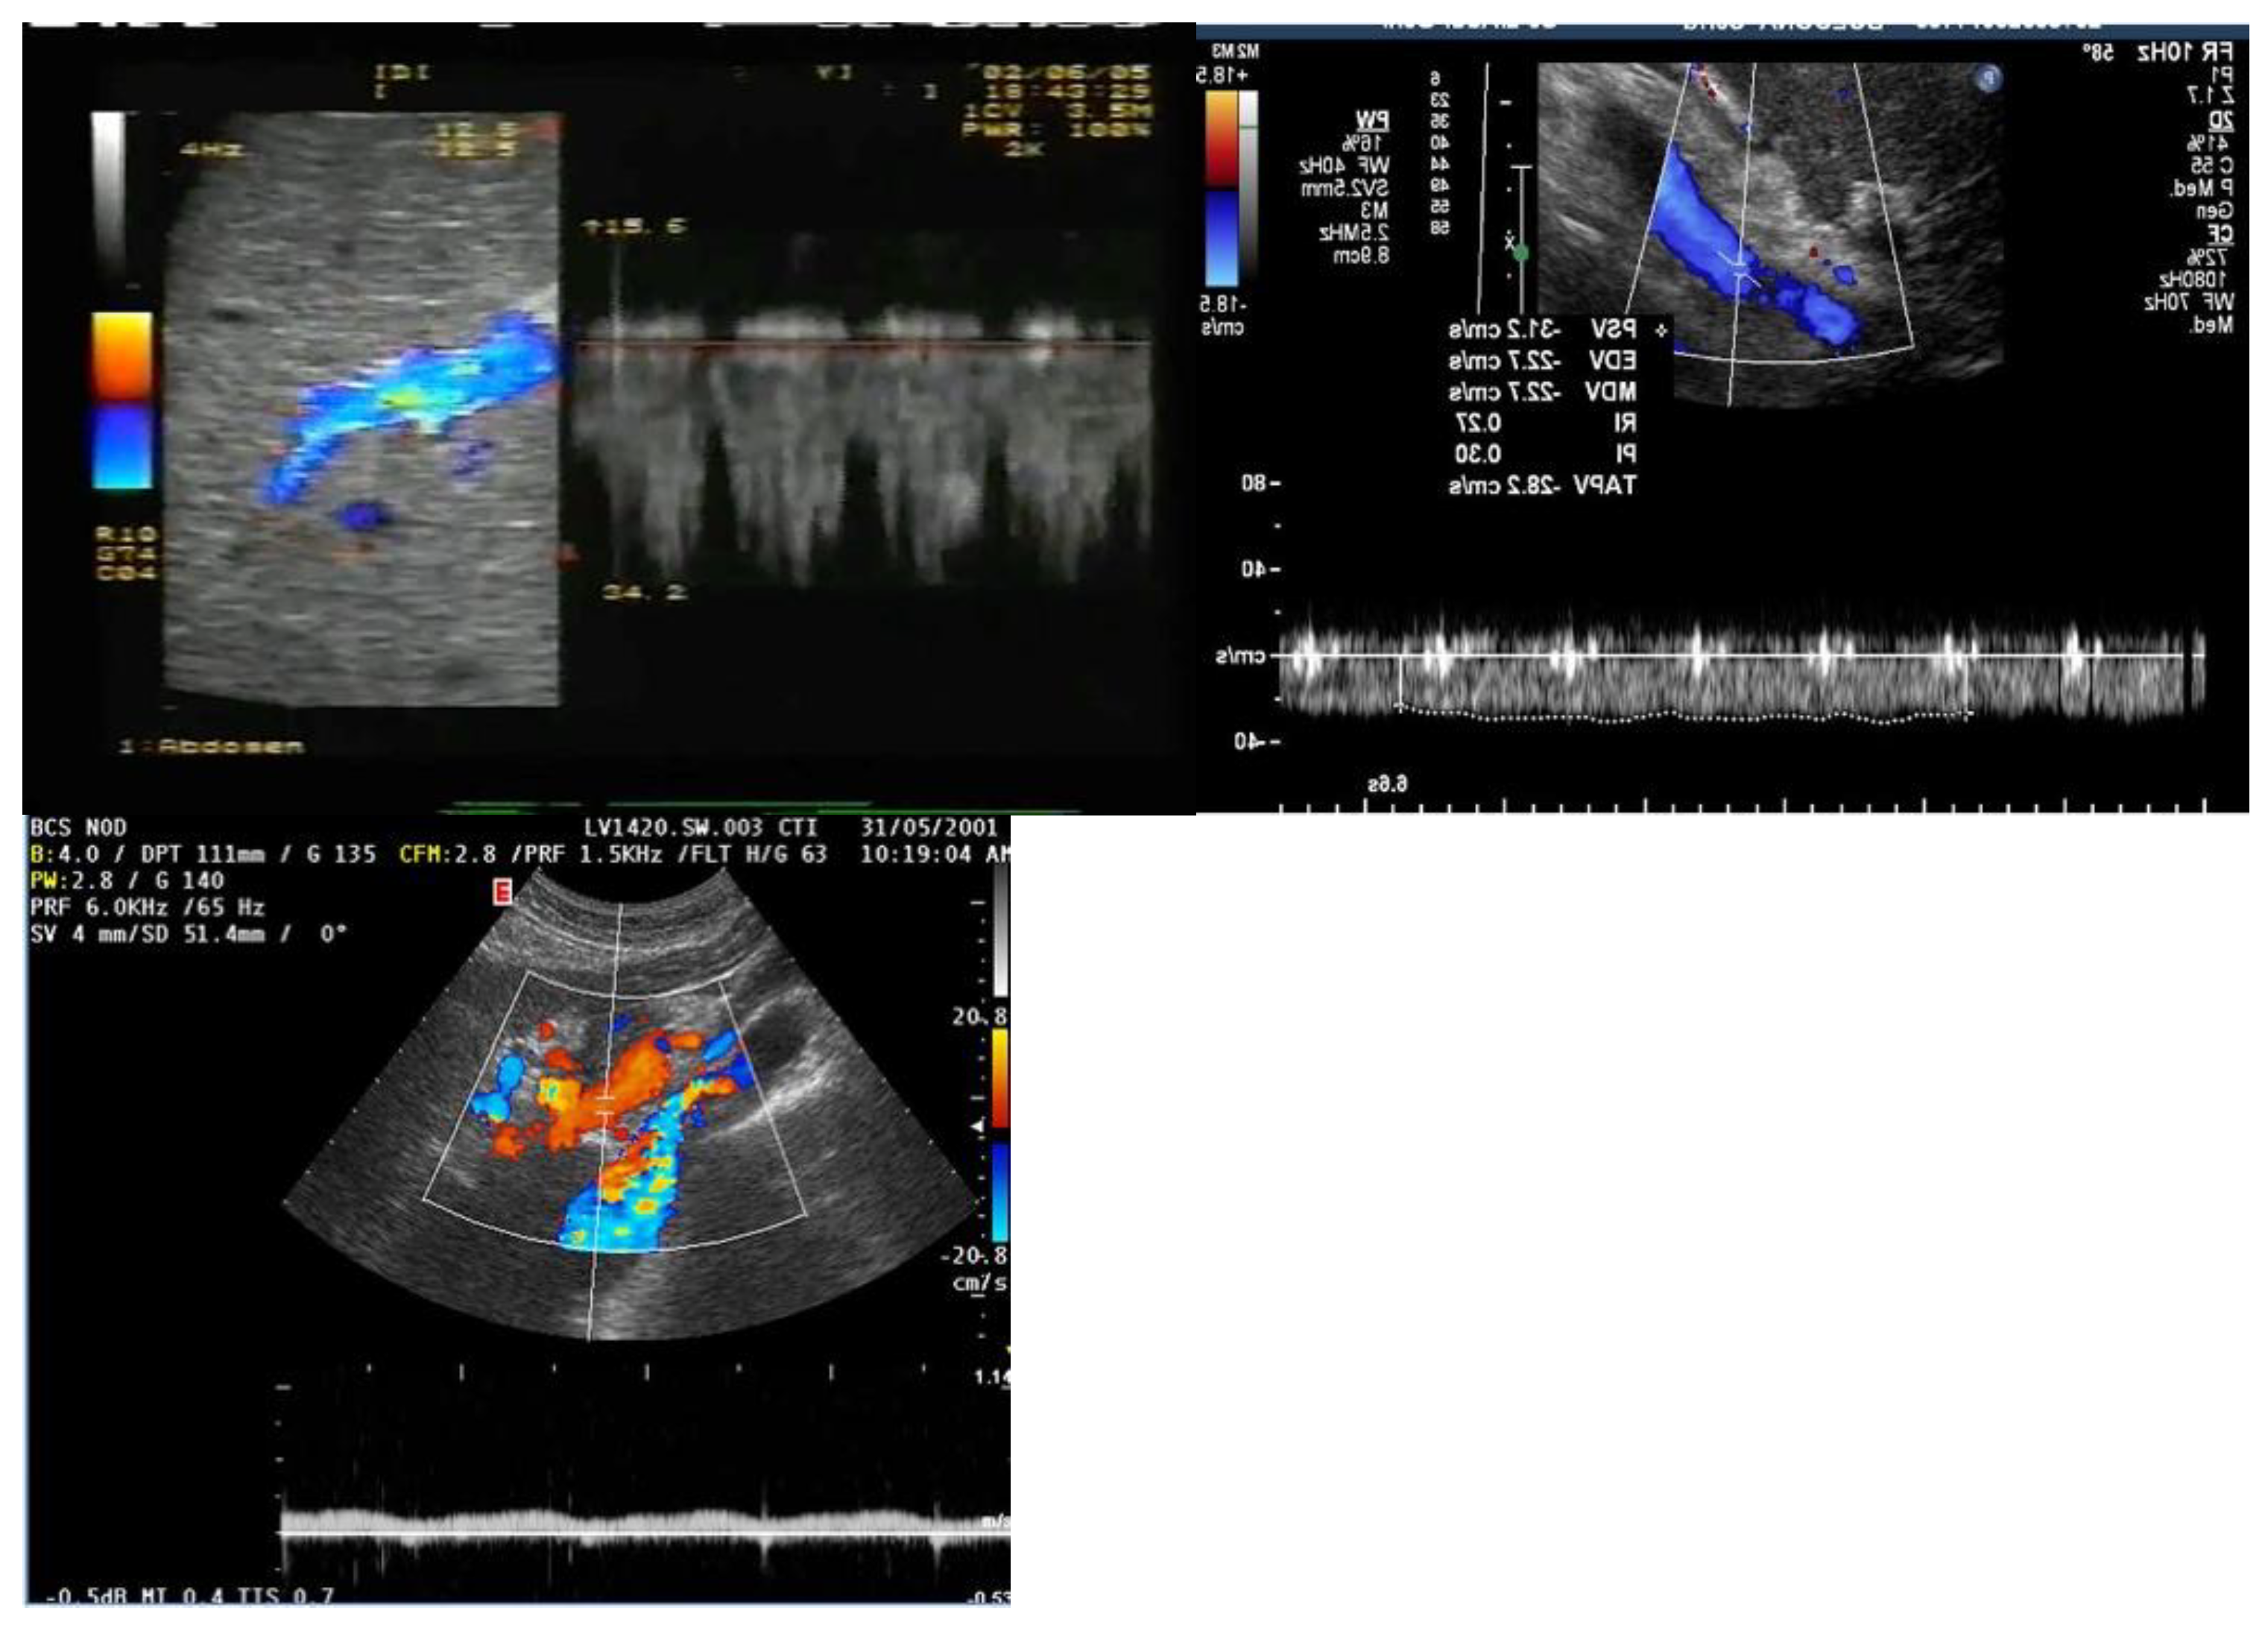

PORTAL VEIN:

4. Absent (Aphasic) Portal Venous Flow:

HEPATIC VEINS:

- Hosoki, T.; Arisawa, J.; Marukawa, T.; Tokunaga, K.; Kuroda, C.; Kozuka, T.; Nakano, S. Portal blood flow in congestive heart failure: pulsed duplex sonographic findings. Radiology 1990, 174, 733-736. [CrossRef]

- Abu-Yousef, M.M.; Milam, S.G.; Farner, R.M. Pulsatile portal vein flow: a sign of tricuspid regurgitation on duplex Doppler sonography. AJR Am J Roentgenol 1990, 155, 785-788. [CrossRef]

- Rengo, C.; Brevetti, G.; Sorrentino, G.; D'Amato, T.; Imparato, M.; Vitale, D.F.; Acanfora, D.; Rengo, F. Portal vein pulsatility ratio provides a measure of right heart function in chronic heart failure. Ultrasound Med Biol 1998, 24, 327-332. [CrossRef]

- Catalano, D.; Caruso, G.; DiFazzio, S.; Carpinteri, G.; Scalisi, N.; Trovato, G.M. Portal vein pulsatility ratio and heart failure. J Clin Ultrasound 1998, 26, 27-31. [CrossRef]